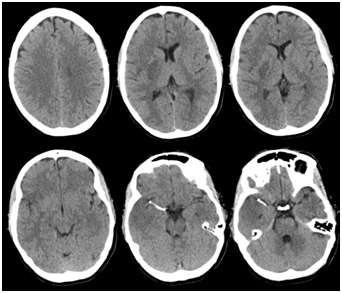

A 36-year-old Caucasian woman presented to the Emergency Department after she was found down on floor, at her home. She had a history of bipolar disorder, no head trauma or vascular risk factors. She was last seen normal about six hours prior to her arrival to the hospital. Upon neurological examination, she was noted to have dense left hemiparesis, forced right gaze deviation and severe dysarthria, the National Institutes of Health Stroke Scale (NIHSS) was 10. A computerized tomography of the head demonstrated a hyperdense right middle cerebral artery (MCA) and no other obvious hyperdensities associated. An emergent magnetic resonance imaging (MRI) of the brain was performed (Figure 1). The MRI of the brain demonstrated early ischemic changes in the right hemisphere, less than one third of the right middle cerebral artery vascular territory, the MRI angiography showed an occlusion of the right M1 segment and an intramural hematoma was also noted in the right M1 segment. Knowing this information, the patient was emergently taken to the angio suite and the diagnosis was made of right M1 occlusion due to an intracranial dissection (Figures 2A–2C).

Figure 1 Magnetic resonance imaging (MRI). (A-C) Diffusion weighted imaging (DWI), axial view demonstrating early ischemic changes in the right hemisphere. (D) Vessel wall MRI, sagittal view showing an intramural hematoma in M1 segment of the right middle cerebral artery (MCA).